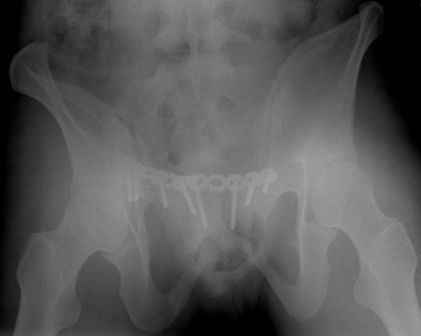

Спасибо за полезные советы! По inlet и outlet обнаружили перелом крестцас той-же стороны. Сегодня прооперировали реконструктивной пластиной с перекрытием симфиза, крестец, увы, фиксировать было нечем - оставили так (тем более, что грубой дислокации там нет). Рентгенограммы выложу позже.

Серия до- и послеоперационных снимков этой пациентки. Хотя бы post factum обсудить. Не знаю, что можно сделать с задними отделами стержневым аппаратом, но три крепких парня открытым путем с помощью "волшебных" слов еле-еле смогли отрепонировать - сзади все было очень ригидно!

я бы остановился на передней раме, операция - 30 мин, в таком варианте вроде бы репозиция - ничего, но когда давать нагрузку, ведь в лонном сочленении тоже есть подвижность? а если не давать - зачем операция?